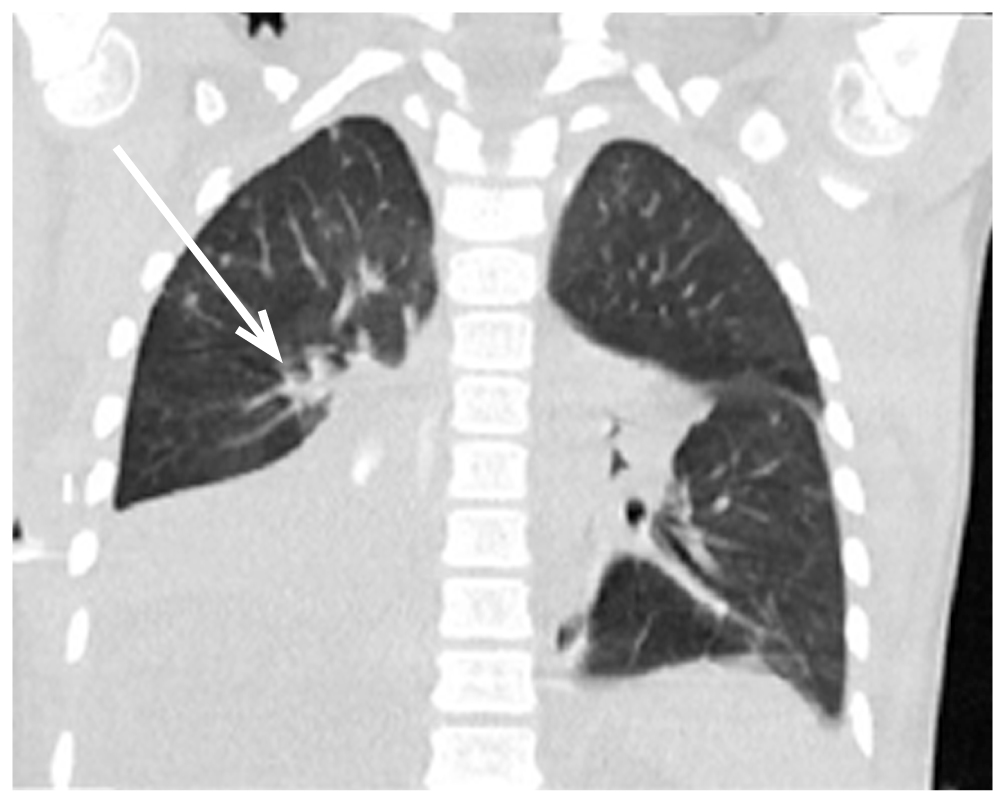

После окклюзии промежуточного бронха сброс воздуха по дренажам прекратился, верхняя доля правого лёгкого полностью расправилась, сохранялся ателектаз средней и нижней долей правого лёгкого, пневмоторакс купировался. Плевральный дренаж во 2 межреберье был удалён. В послеоперационном периоде отмечен регресс дыхательной недостаточности: pCO2 55 мм рт. ст., pO2 90–92 мм рт. ст., сатурация 99–100%. По данным СКТ на 6 сут после выполнения ЛТБС в просвете промежуточного бронха справа определялось инородное тело (блокаторы), полностью перекрывающее просвет бронха. Средняя и нижняя доли резко уменьшены в объёме, бронхиальное дерево и паренхима их полностью безвоздушны, пневмомедиастинум и воздушная эмфизема мягких тканей регрессировали (рис. 4).

Рис. 4. Спиральная компьютерная томография на 6 сут после ларинготрахеобронхоскопии: ателектаз средней и нижней долей правого лёгкого (стрелка).

Fig. 4. Spiral computed tomography 6 days after laryngotracheobronchoscopy: atelectasis of the middle and lower lobes of the right lung (arrow).